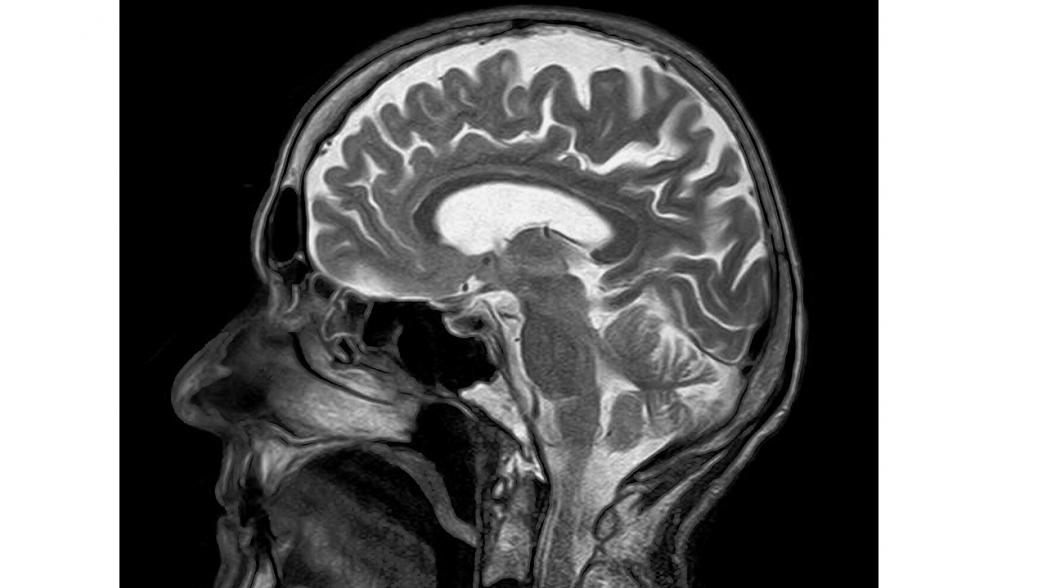

В Германии разрабатывается сверхдешевая портативная МРТ-система

Еще находящаяся в стадии разработки система DeepSpin будет представлять собой МРТ-систему нового типа, которая будет существенно меньше по весу и размеру существующих систем, а ее цена составит всего лишь долю стоимости современных МРТ-аппаратов. Для того, чтобы это было осуществимо, специалисты компании разработали новую технологию антенны, а также программное обеспечение управления работой системы на основе алгоритмов искусственного интеллекта.

Вместо того, чтобы комбинировать дорогостоящее оборудование со стандартным программным обеспечением, как это делается на обычных МРТ-сканерах, новая система позволяет получать клиническую информацию такого же качества, применяя очень сложные алгоритмы на упрощенном аппаратном обеспечении, тем самым снижая стоимость системы на порядки величины.

Разработчики утверждают, что их разработка обладает производительностью и качеством, такими же как стандартные МРТ-аппараты, не требует специального обслуживания, поскольку не использует гелий и может применяться в любом месте, включая больничные палаты.